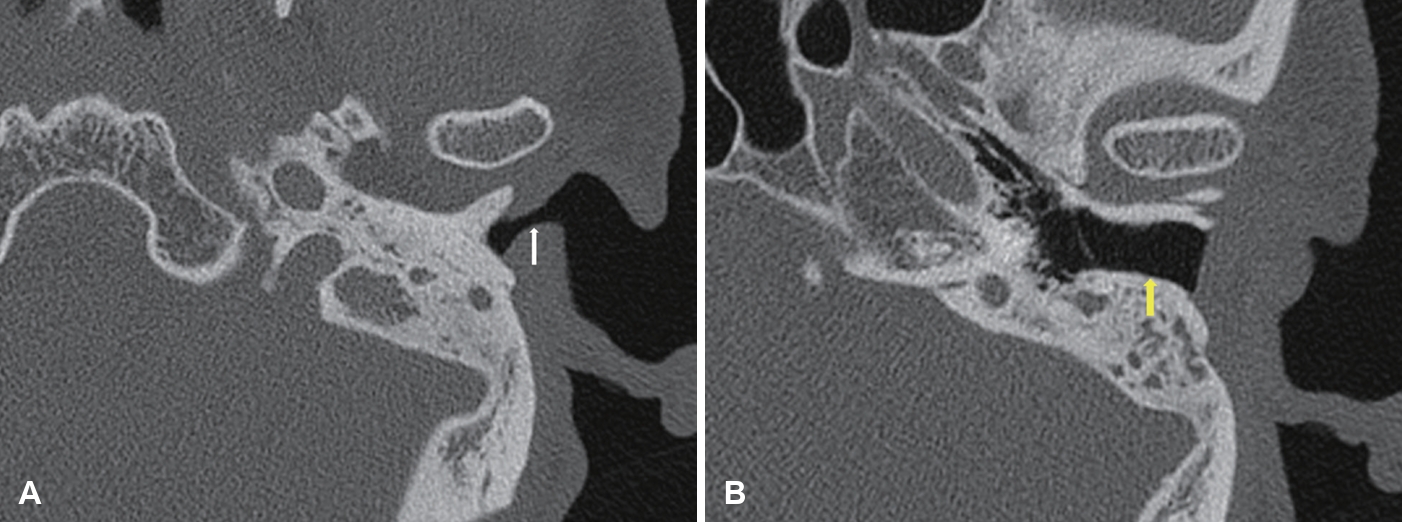

단독 외이도성형술이 모든 이루 환자에게 적용되는 것은 아니다. 고막 천공이 크거나 만성 감염, 진주종 등 중이 병변이 동반된 경우에는 고실성형술이나 유양돌기절제술과 같은 근본적 치료가 우선되어야 한다. 그러나 이런 환자에서도 수술 전 외이도 입구가 좁아 이루 배출이 어려운 경우, 중이 수술과 외이도성형술을 병행해 수술 직후 건조 유지와 환기 기능을 향상시킬 수 있다(Fig. 4).